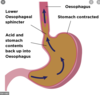

In Barrett’s Oesophagus the cells lining the lumen at the distal end of the oesophagus undergo metaplasia, which is the replacement of one cell type to another from the basal cells due to a stimulus. The normal non keratinising stratified squamous epithelium of the lower oesophagus undego metaplasia and become columnar cells. What is the pathological cause of this?

- acid from stomach causes oesophagitis

- long standing gastro-oesophageal reflux disease

In the image below we can see a healthy Oesophageal- gastric junction (OGJ) and a OGJ in a patient with Barrett’s Oesophagus. Between A and B, which is the healtht and which is the Barrett’s Oesophagus?

- A = normal

- B = Barrett’s Oesophagus